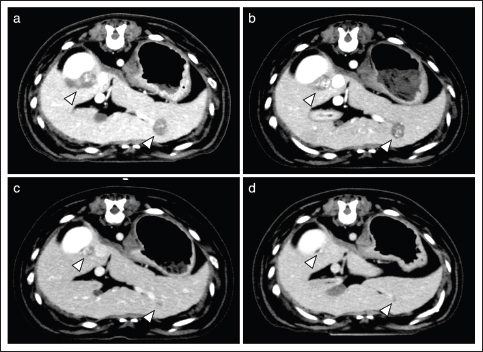

Case 3 was untreated for 1 year after surgical resection of the primary lesion, but metastatic lesions were newly identified in the liver. Therefore, the dog was treated with temozolomide 48 days before the initiation of AP combination therapy. However, because of disease progression, the dog was treated with five doses of DOX and concomitant propranolol. After the first dose of DOX, some tumor lesions showed marked shrinkage and largely disappeared (Fig. 1). While the disease remained in remission, the dog died on day 113 because of aspiration pneumonia.

Interestingly, the tumor sizes of the metastatic lesions were reduced in two of the four dogs in which CBs were observed (Table 1). In case 3, the tumor shrank after the initiation of AP combination therapy, even though the tumor had not been responsive to conventional therapy (Fig. 1). Considering such a clinical course, it seems reasonable to conclude that AP combination therapy showed a remarkable anti-tumor effect in these dogs with HSA. Although previous studies have shown that conventional anthracycline-based therapies may contribute to prolonged survival time of dogs with HSA (Alvarez et al., 2013; Finotello et al., 2017; Sharun, 2019; Griffin et al., 2021), there are few reports demonstrating a significant reduction of tumor lesions in dogs with advanced HSA based on these treatments. Additionally, the high CB rate (80%) in the present study is comparable only to that of the aggressive chemotherapy protocols using vincristine, DOX, and cyclophosphamide with severe adverse effect risks (e.g., sepsis) (Alvarez et al., 2013). Considering the safety described above, our findings on anti-tumor responses indicate the possibility that AP combination therapy may contribute to the establishment of useful and well-tolerated treatment strategies in dogs with stage 3 HSA.

Fig. 1. Transition of liver metastatic lesions (Case 3). CT images are shown before (a), and on day 22 (b), 49 (c), and 77 (d) after initiation of the AP combination therapy. Arrowheads indicate metastatic lesions.